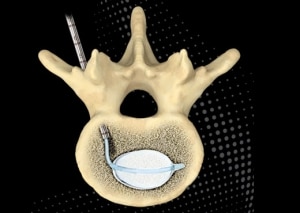

Vertebral compression fractures (VCFs) are the most common fracture in patients with osteoporosis.1 Although painful and debilitating, VCFs often go untreated. To help care for this patient population, Merit Medical innovated the Arcadia, an intuitive balloon-assisted vertebral augmentation (kyphoplasty) system. Designed to be used with the steerable PowerCURVE® Navigating Osteotome, the Arcadia offers several unique benefits when treating patients with painful VCFs.

Bipedicular Footprint, Unipedicular Approach

Steerability allows the Arcadia system to target a specific location within the vertebra using a transpedicular approach through a single skin incision. Once past the pedicle body junction, the ability to articulate the device allows accurate navigation to the biomechanically critical important anterior and middle third of the vertebra, resulting in a bipedicular cement footprint byway of a less invasive unipedicular approach.

Compared to curved devices manufactured with a predetermined shape which limits trajectory based solely on access into the vertebral body, steerability allows physicians to change trajectory simply by turning the gray handle of the PowerCURVE and Arcadia after accessing the vertebra.

This provides a targeted single-access ability to cross the vertebral midline, enabling optimal balloon tamp positioning and cavity creation. The steerable osteotome, when used alone, can provide targeted channel creation, simultaneously sparing healthy cancellous bone and maximizing surface area to facilitate cement interdigitation. In addition, targeted cavity creation supports the controlled delivery of high-viscosity cement with optimal cement fill.